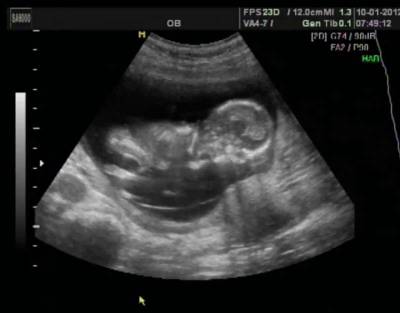

Ультразвуковая диагностика

Тогда врач назначает исследование на 16-22 , 32-34-й неделях – для уточнения диагноза или его снятия.

Именно этот вид диагностики с точностью может определить все нарушения развития разных систем и органов эмбриона.

При нормальном развитии плода врач четко на экране видит:

- сформированную носовую кость;

- толщину воротникового пространства;

- сердечную мышцу;

- мозг;

- все органы;

- правильно сформированные конечности и так далее.

Если врача настораживает какие-либо визуальные наблюдения за плодом, то он назначает дополнительные методы диагностики.